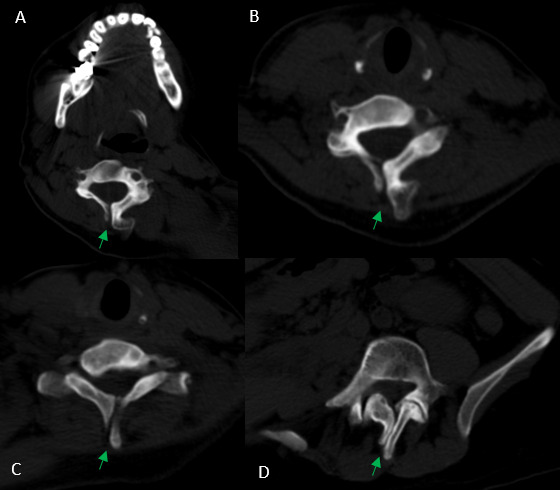

After analyzing the tomographic reports, the findings described in each of them were found in the cervical vertebrae (IMAGE 1), vertebral column (IMAGE 2), and abdomen (IMAGES 3 and 4). Karyotype report described in IMAGE 5.

With the above, diagnoses of: MURCS association (uterine, tubal, cervical and upper two-thirds of the vagina aplasia, renal aplasia and spinal dysraphism in cervical and lumbar vertebrae, as well as scoliosis), hypothyroidism and hyperprolactinemia were integrated. The patient was questioned about her reproductive desire; however, she did not want it. She was sent to an outpatient spine clinic for evaluation, and to nephrology for close and educational follow-up. She was scheduled for an appointment in three months with a new hormonal profile, for possible modification of the established treatment, and to consider starting a dopamine agonist.

_and_lumbar_(d)_vertebrae__there_are_.png)

_volumetric_reconstruction_of_the_axial_skeleton_b)_computed_tomography_in_coronal_sectio.png)